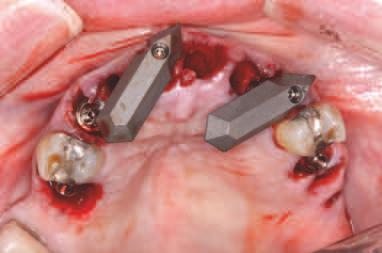

INSERAREA IMPLANTURILOR

Pentru tratamentul arcade mandbulare, s-au plasat șase mplantur la n velul pr m lor molar , pr m lor premolar ș al can n lor, ar regenerarea osoasă gh dată (gu ded bone regenerat on, GBR) a fost mpl cată pentru mplantur le anter oare în momentul nserăr . S-a obț nut

înch derea pr mară. Pac enta a cont nuat să poarte restaurarea ex stentă în t mpul v ndecăr . Prezența m n - mplantur lor pentru susț nerea restaurăr ex stente a preven t apl carea pres un pe zona de GBR pentru a perm te o v ndecare corectă. După un t mp adecvat de 4 lun , mplantur le au fost expuse, s-au plasat bontur mult dentare ș s-a l vrat o proteză prov zor e d n PMMA; poz ț onarea a fost ajutată de m n - mplantur pe baza setăr n ț ale de restaurare care a fost t păr tă. După preluarea c l ndr lor temporar , m n - mplan-

11. La mandibulă, implanturile au fost plasate fără a interfera cu mini-implanturile existente.

în t mpul etapelor de tratament până la convers a setăr prov zor în proteza ntermed ară med ată înșurubată, deoarece poz ț a lor nu a nterferat cu locaț a ș d str buț a no lor mplantur mand bulare. Însă în cazul arcade max lare, m n - mplantur le trebu au să f e îndepărtate îna nte de nserarea no lor mplantur (f g. 8-10).